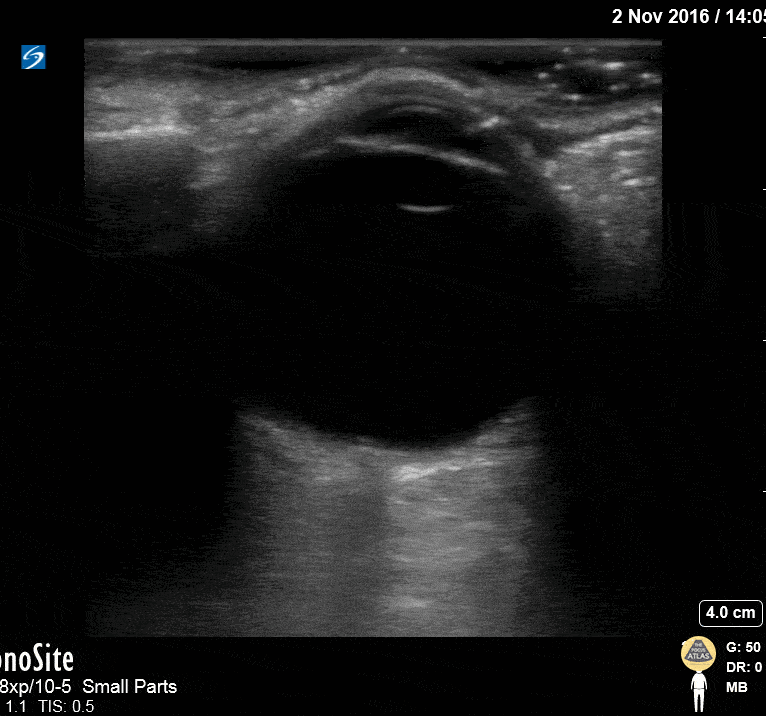

Orbital - Normal Eye Anatomy

This image of the eye shows the following structures, from superficial to deep: eyelid, cornea (hyperechoic), anterior chamber (anechoic), iris (hyperechoic), lens (hyperechoic), vitreous (very large anechoic area), retina (flush with the posterior wall of the globe, not visible as a distinct structure under normal conditions), optic nerve sheath (hypoechoic structure extending midline perpendicularly from the globe at the bottom of the image). Hannah Kopinksi and Dr. Lindsay Davis - NYU Emergency Medicine